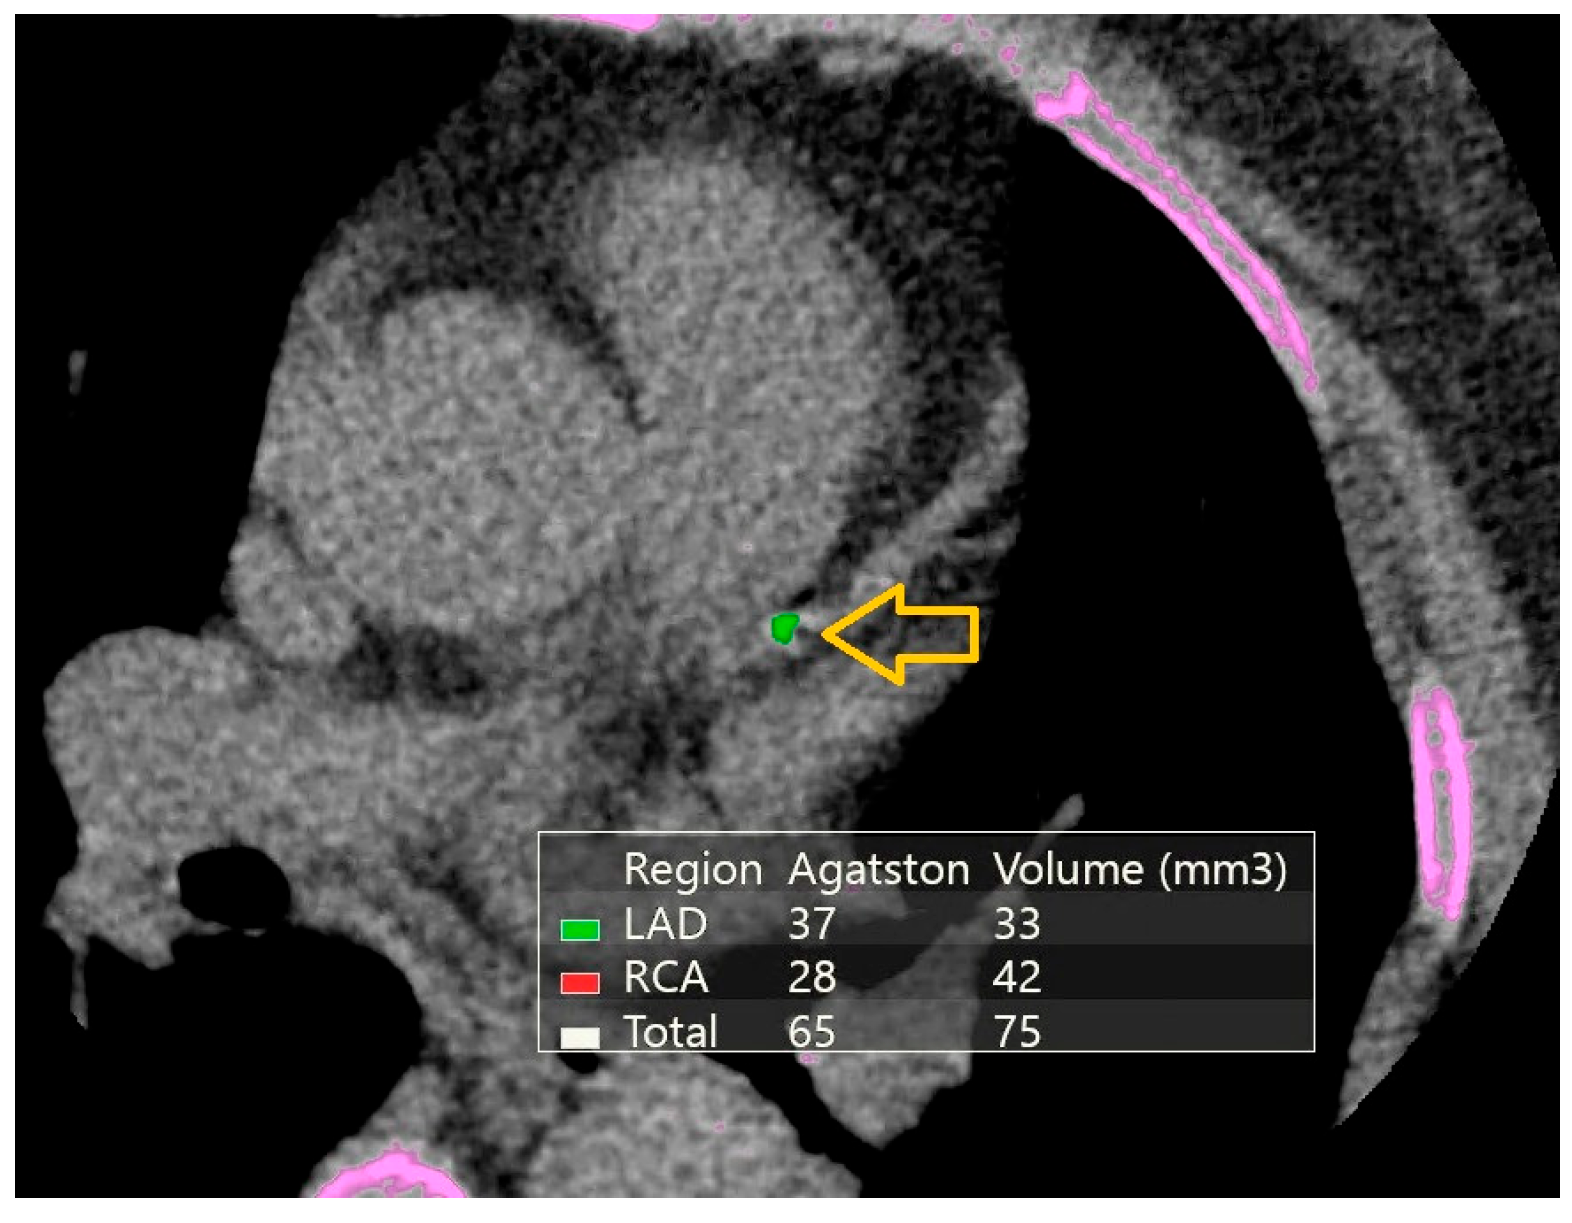

- Agatston, A.S.; Janowitz, W.R.; Hildner, F.J.; Zusmer, N.R.; Viamonte, M., Jr.; Detrano, R. Quantification of coronary artery calcium using ultrafast computed tomography. J. Am. Coll. Cardiol. 1990, 15, 827–832. [Google Scholar] [CrossRef] [PubMed]

| Agatston calcium score, median (IQR) | 59.5 (33.5–206.2) | 87.5 (40–189.5) | 1 b |

| Calcium volume score, median (IQR) | 69 (39.7–206.5) | 86 (44–200.2) | 0.920 b |